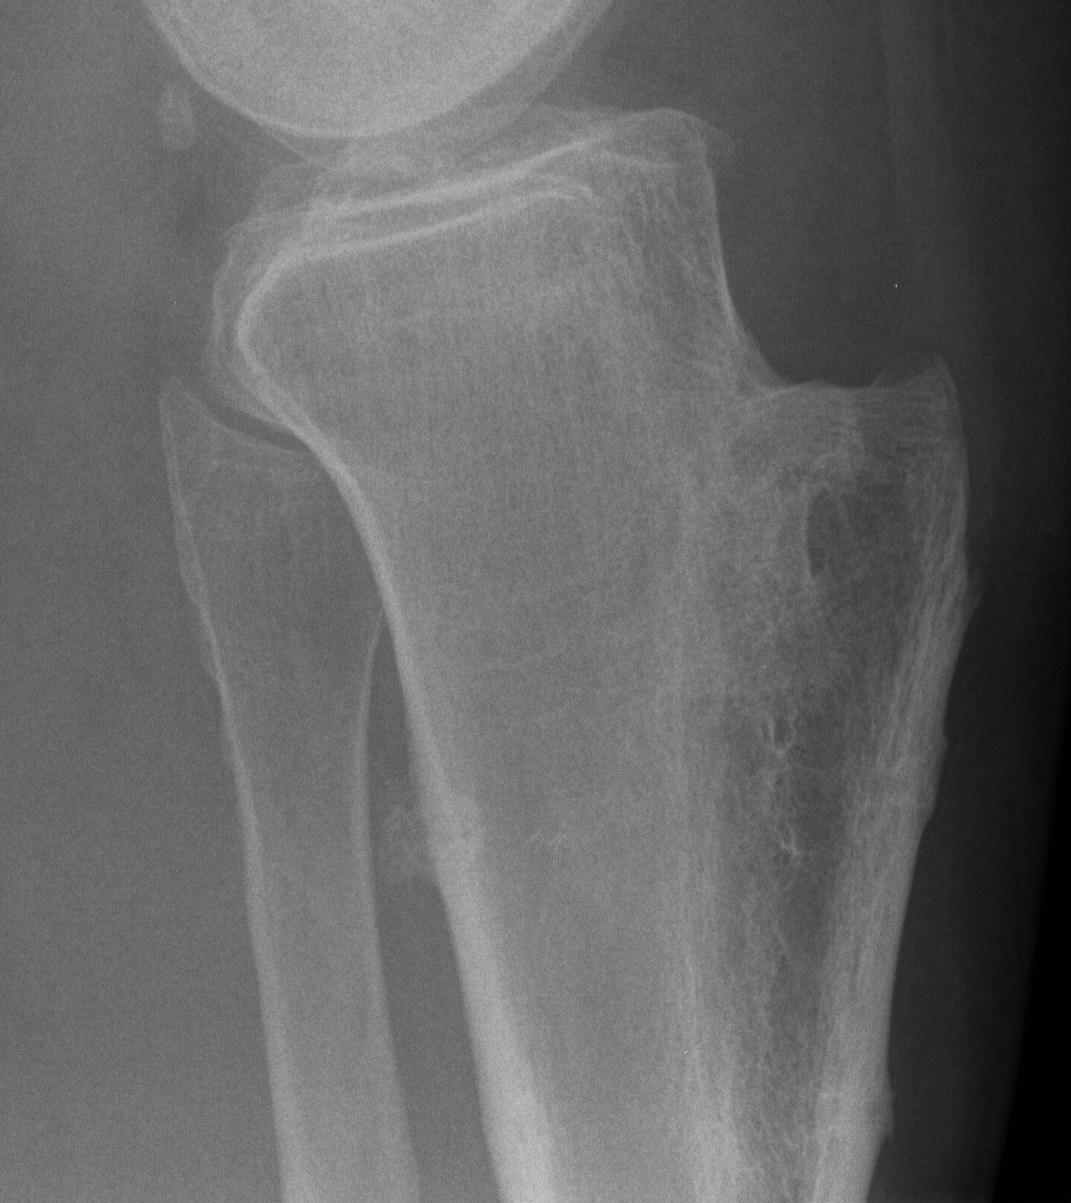

Tibial tuberosity Osteotomy

www.boneschool.com/tibialtuberosityosteotomy

Options

Medialization / Elmslie-Trillat

Anteromedialization / Fulkerson

Elevation / Maquet

Fulkerson Maquet

Tibial tuberosity osteotomy (TTO)